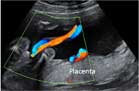

Ecografía Embarazo 2D y 3D